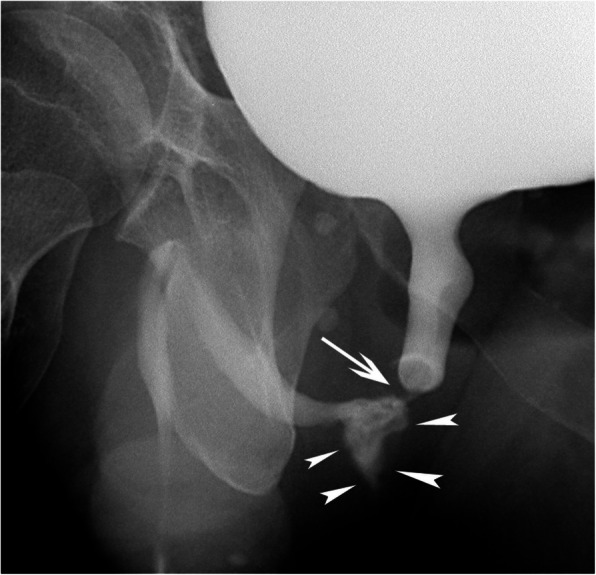

Fig. 2.

Retrograde urethrography. Oblique plain film after retrograde contrast injection clearly demonstrates the post-traumatic stricture (arrow) and the contrast extravasation (arrowheads) at the posterior part of the pars bulbosa urethrae